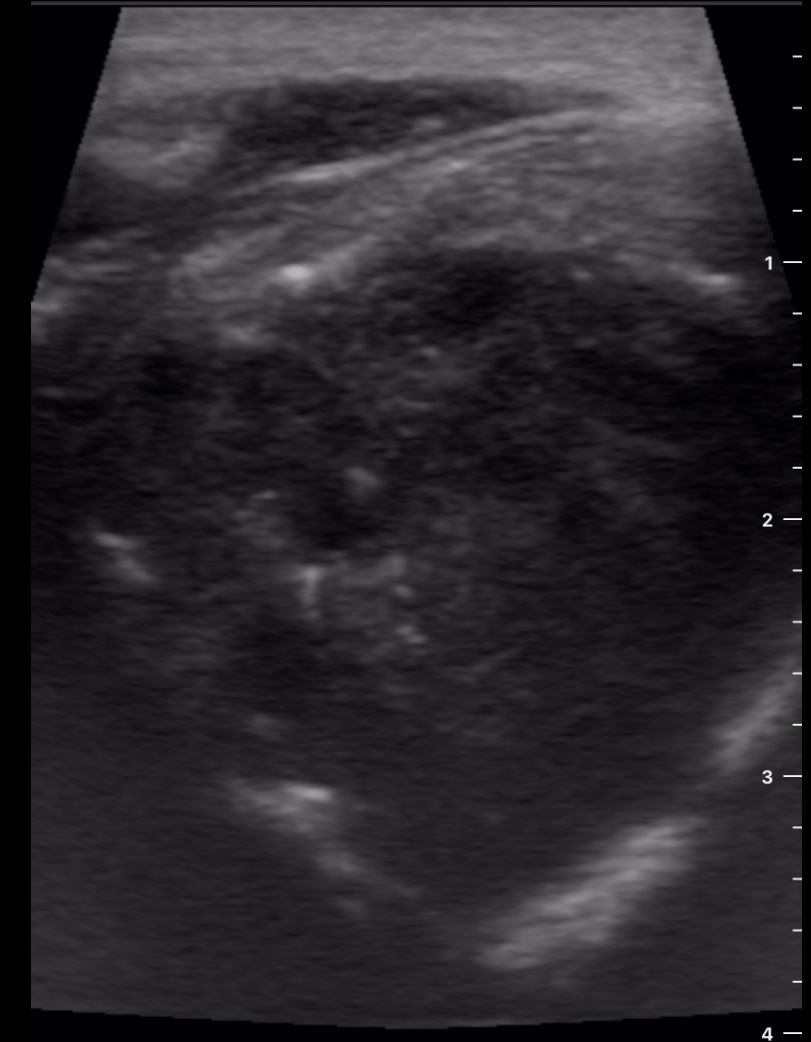

Se decide realizar ecografía clínica con ecógrafo de bolsillo para poder orientar caso, donde se aprecia tumoración de gran tamaño hipoecoica, heterogénea, con calcificaciones de pequeño tamaño en su interior, dependiente de lóbulo tiroideo derecho, sin poder definir límites inferiores, y sin poder localizar la vena cava inferior pero visualizando imagen de vena trombosada junto al istmo.

Ante la sospecha de cáncer de tiroides y la visualización de trombosis venosa que probablemente corresponda a vena cava inferior por la localización se deriva a Urgencias de Hospital de referencia, describiendo hallazgos y sospecha diagnóstica.